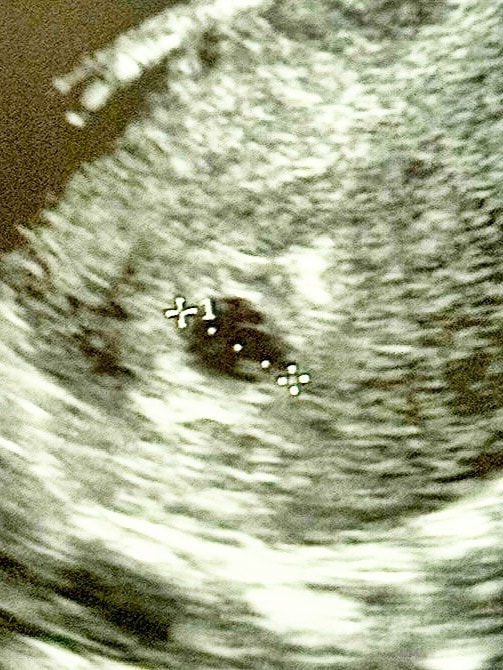

Ангелина, в заключении плодное яйцо 11мм жм 3мм

Если бы было 2 жм то в заключении так и написали бы, указав размеры обоих жм. А поскольку у вас указан 1, то он там 1, не стоит разглядывать эти фотки.

я не вижу два ... думается один